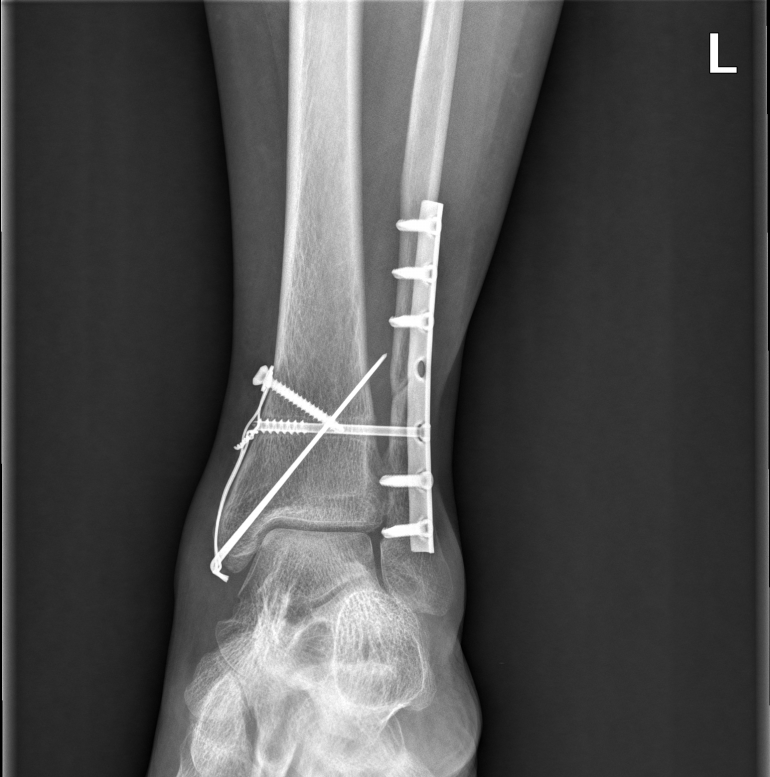

안녕하세요. 오늘 행사는 삼복골절 교통사고 합의 사례입니다.삼복사는 복숭아뼈와 정강이뼈 발목 뒤쪽의 후과를 일컫는 말입니다. 3개의 과(뼈에서 돌출된 부분)를 의미하기 때문에 ‘삼과골절’이라고도 합니다. 덧붙여서 바깥쪽 도골은 경골외과, 안쪽 도골은 비골로 구성됩니다. 위 영상은 전면부이므로 후과골절은 확인이 되지 않습니다. 아래의 X-RAY 영상을 보실 수 있습니다.

피해자는 사고 후 타 병원의 검사 결과 trimal leolar fracture (삼과골절)로 확인되었으며, 수술문제로 상급병원으로 전원 후 관혈적 정복 및 내고정술을 실시하였습니다. 사고로 인한 치료비는 보험사가 지급 보증하므로 걱정하지 마시고, 만약 비급여 치료비를 부담하셨더라도 나중에 영수증 처리가 가능하므로 걱정하지 마시고 치료에만 전념하십시오. 다만 보험사에서 피해자에게 진단서, 수술기록지, 영상판독지, 영상CD 등 다양한 서류를 요구하는 경우가 있는데, 정상적인 지급보증 절차에 필요한 서류는 진단서, 수술기록지 정도이고 영상CD는 추후 후유증 관련 분쟁시 불리할 수 있으므로 추후 제출하는 것이 좋습니다.

피해자 분은 위와 같이 진단을 받고 관혈적 정복 및 내고정술, 변연절제술을 시행한 후 퇴원하여 통원치료를 실시하였습니다. 변연 절제술은 괴사한 부분을 일부 절제하는 것을 말합니다. 삼복골절은 ‘외상성관절염’ 및 ‘발목의 운동각도 제한’ 등 후유증이 잔존하는 경우가 많기 때문에 합의 진행 시 후유장애를 고려하여 절차를 거쳐야 합니다.